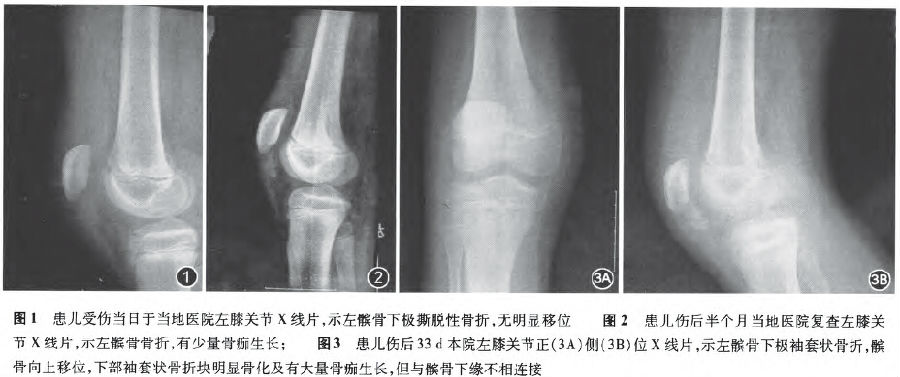

儿童髌骨袖套状骨折误治一例

900x377 - 56KB - JPEG